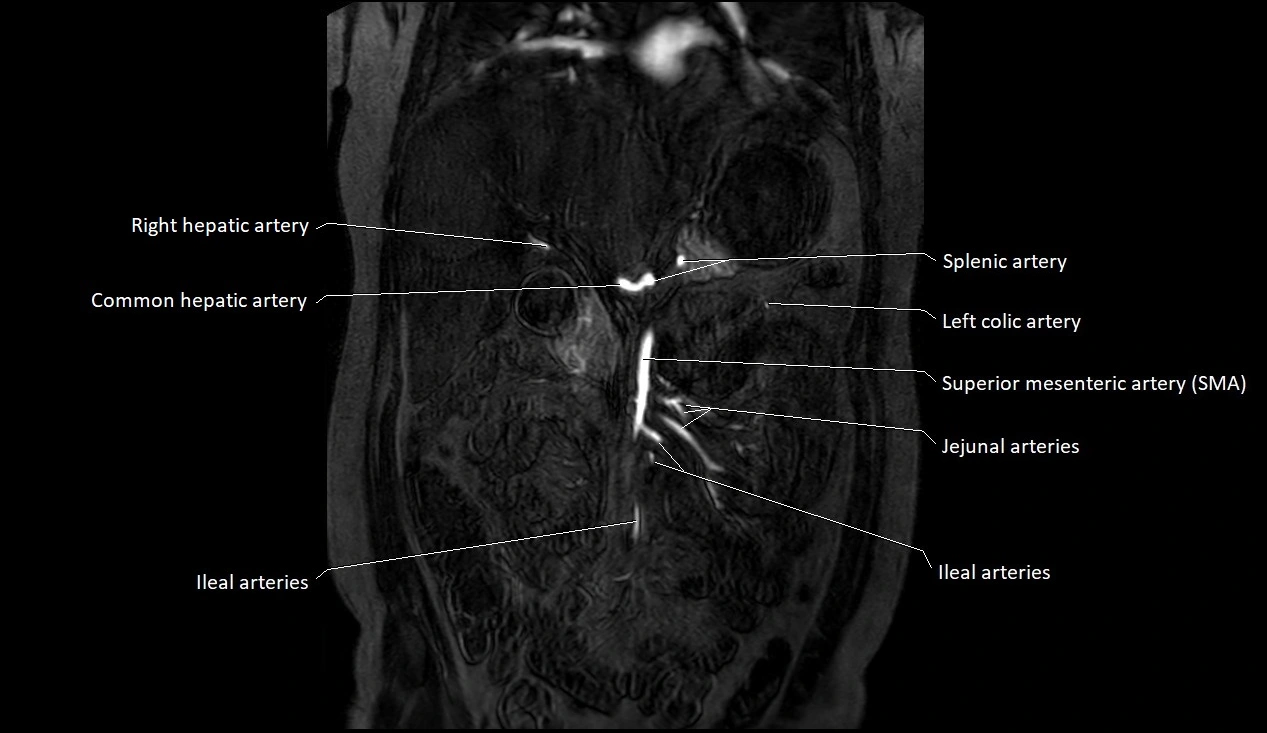

MRI images

image